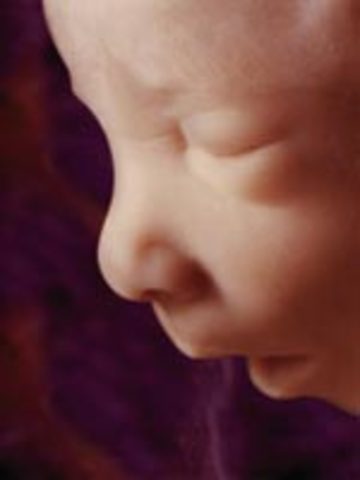

• Week 16: Facial Expressions

Week 16: Facial Expressions

The baby boy or girl is now 12 cm in length at about 3.5 oz in weight. By learning how to breathe, the lungs begin to form and grow. Squinting or frowning is now possible and lots of movement can be made.